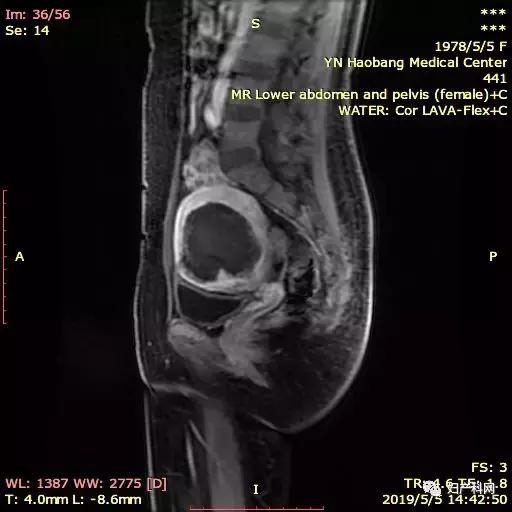

因为这个患者子宫比较大,同时还有比较重的贫血貌,所以就诊时查了一下血常规仅有60+g/L,这样的情况下直接治疗不仅难度大,术后恢复也相对比较慢。所以我们先给予了患者一只10.8mg的诺雷德,希望她能够这几个月不来月经,避免进一步的丢失,同时开始口服铁剂补血,从1月底患者就诊到4月安排治疗,3个月的时间血色素恢复到了102g/L,子宫腺肌症的范围也从1月的12×7×11cm缩小到了8×5×7.5cm,治疗当天我们使用经皮的微波治疗,功率50w治疗6min10s,60w治疗9min36s,进行超声造影消融满意,于宫腔内放置了曼月乐环1枚。